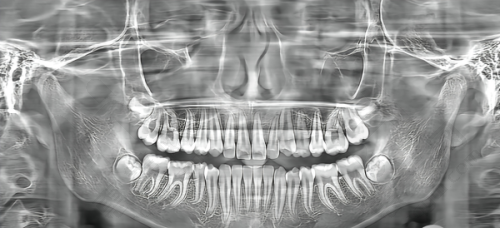

合肥松丰齿科是一家私立医院,在当地口腔医疗市场有一定地位。它位列合肥十家便宜靠谱私立口腔医院第七,地址位于瑶海区胜利路 88 号元一时代广场,位置优越。其由上海松丰齿科集团打造,有国内外化诊疗服务,技术和设备精良。涵盖牙齿矫正、种植等多种诊疗项目,医生会制定个性化方案。价格适中,还常开展公益活动,如免费种牙月。私立属性使其运营和服务更灵活,注重患者体验,为当地民众提供了多样化口腔诊疗选择。

合肥松丰口腔的诊疗项目

合肥松丰口腔涵盖了多种口腔诊疗项目,其中牙齿矫正和牙齿种植是比较受关注的项目。牙齿矫正可以帮助患者改善牙齿排列不齐的问题,不仅能提升美观度,还对口腔健康有益。而牙齿种植则为牙齿缺失的患者提供了有效的解决方案,让患者能够修复正常的咀嚼功能。

医院的专精医生团队会根据患者的具体情况,制定个性化的治疗方案,确保每个患者都能得到更适合自己的治疗。无论是青少年的牙齿矫正,还是中老年人的牙齿种植,合肥松丰口腔都有相应的技术和经验来应对。